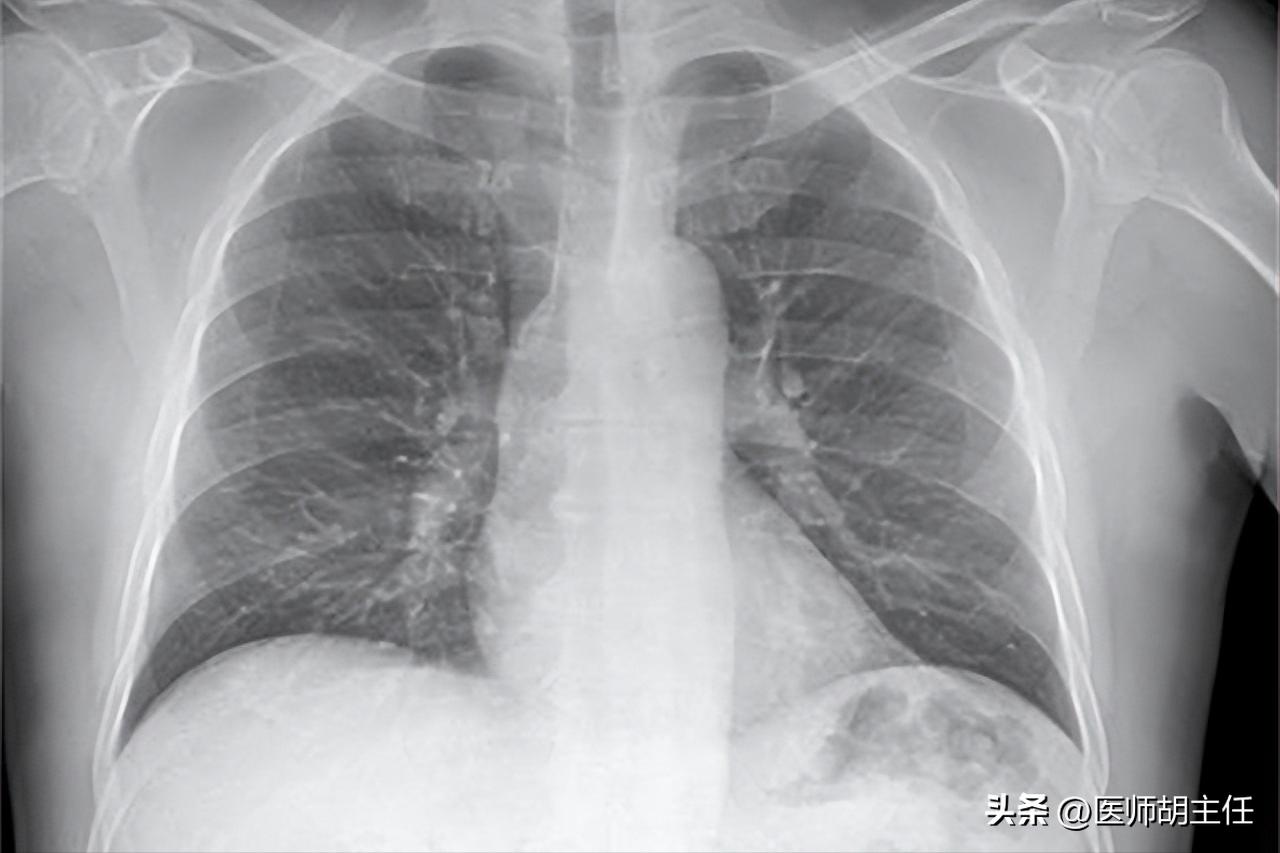

3、 X光筛查肺癌

由于 肺癌的常发生于隐蔽部位和且病灶微小 ,所以通常是通过高分辨率的器械才能检查出来。

由于X光分辨率较低,所以对于早期肺癌的一些小病灶或隐秘部位的病灶检出率比较低,所以 筛查肺癌一般不用X光,而用低剂量的CT。

CT对于肺癌查出的优势是,就算是小于1cm的病灶也能够筛查出来, 对于早期肺癌不仅能提高筛查率,也能避免遗漏隐蔽部位的病灶。

所以下一次查肺癌,医生让你去做CT,不要以为医生在忽悠你,这是正确的。